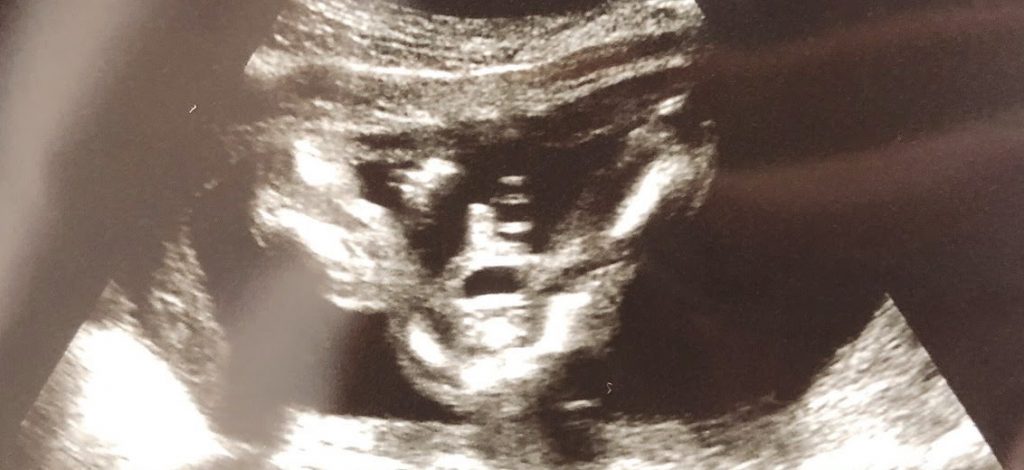

朝から嬉しい知らせ 今朝、なゆちは早起きして産婦人科へ行きました。 三度目の産科検診です。 妊娠20週に突入し、 「そろそろ性別がわかる頃らしい」 とワクワクで出発。 ソワソワ仕事をしながら待っていると、 約1時間後くら … 続きを読む 台湾生活-Day10「小豆の性別が判った記念の日」